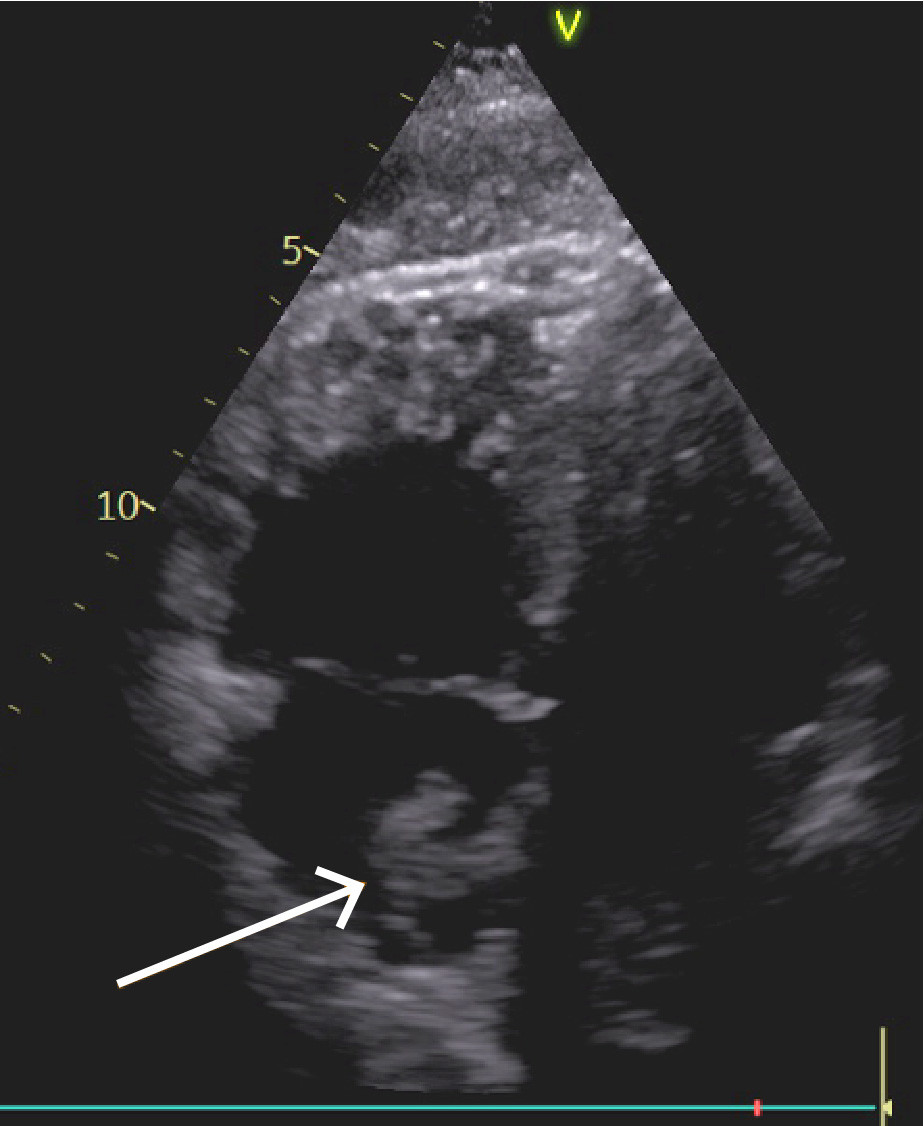

Orienterende ekkokardiografi viste betydelig dilatasjon av høyre ventrikkel, der høyre ventrikkel (RV) hadde klart større diameter enn venstre (LV), med en RV/LV-ratio 1,3. Normalt ratio er 0,66, og alt over 1,0 er klart patologisk (1). Høyre ventrikkel fremstod med redusert langaksefunksjon, TAPSE (tricupid annular plane excursion) målt til 10 mm (normalt > 17). I høyre atrium ble det observert en stor flagrende masse, som ga mistanke om trombe (figur 3, video). Venstre ventrikkel hadde svekkede kontraksjoner i septum og var komprimert fra den dilaterte høyre hjertehalvdelen. Dopplervurderinger var forenlig med underfylling av venstre ventrikkel. Aorta ascendens var normaldimensjonert, men det ble sett en aortainsuffisiens som var vanskelig å gradere i akuttsituasjonen.